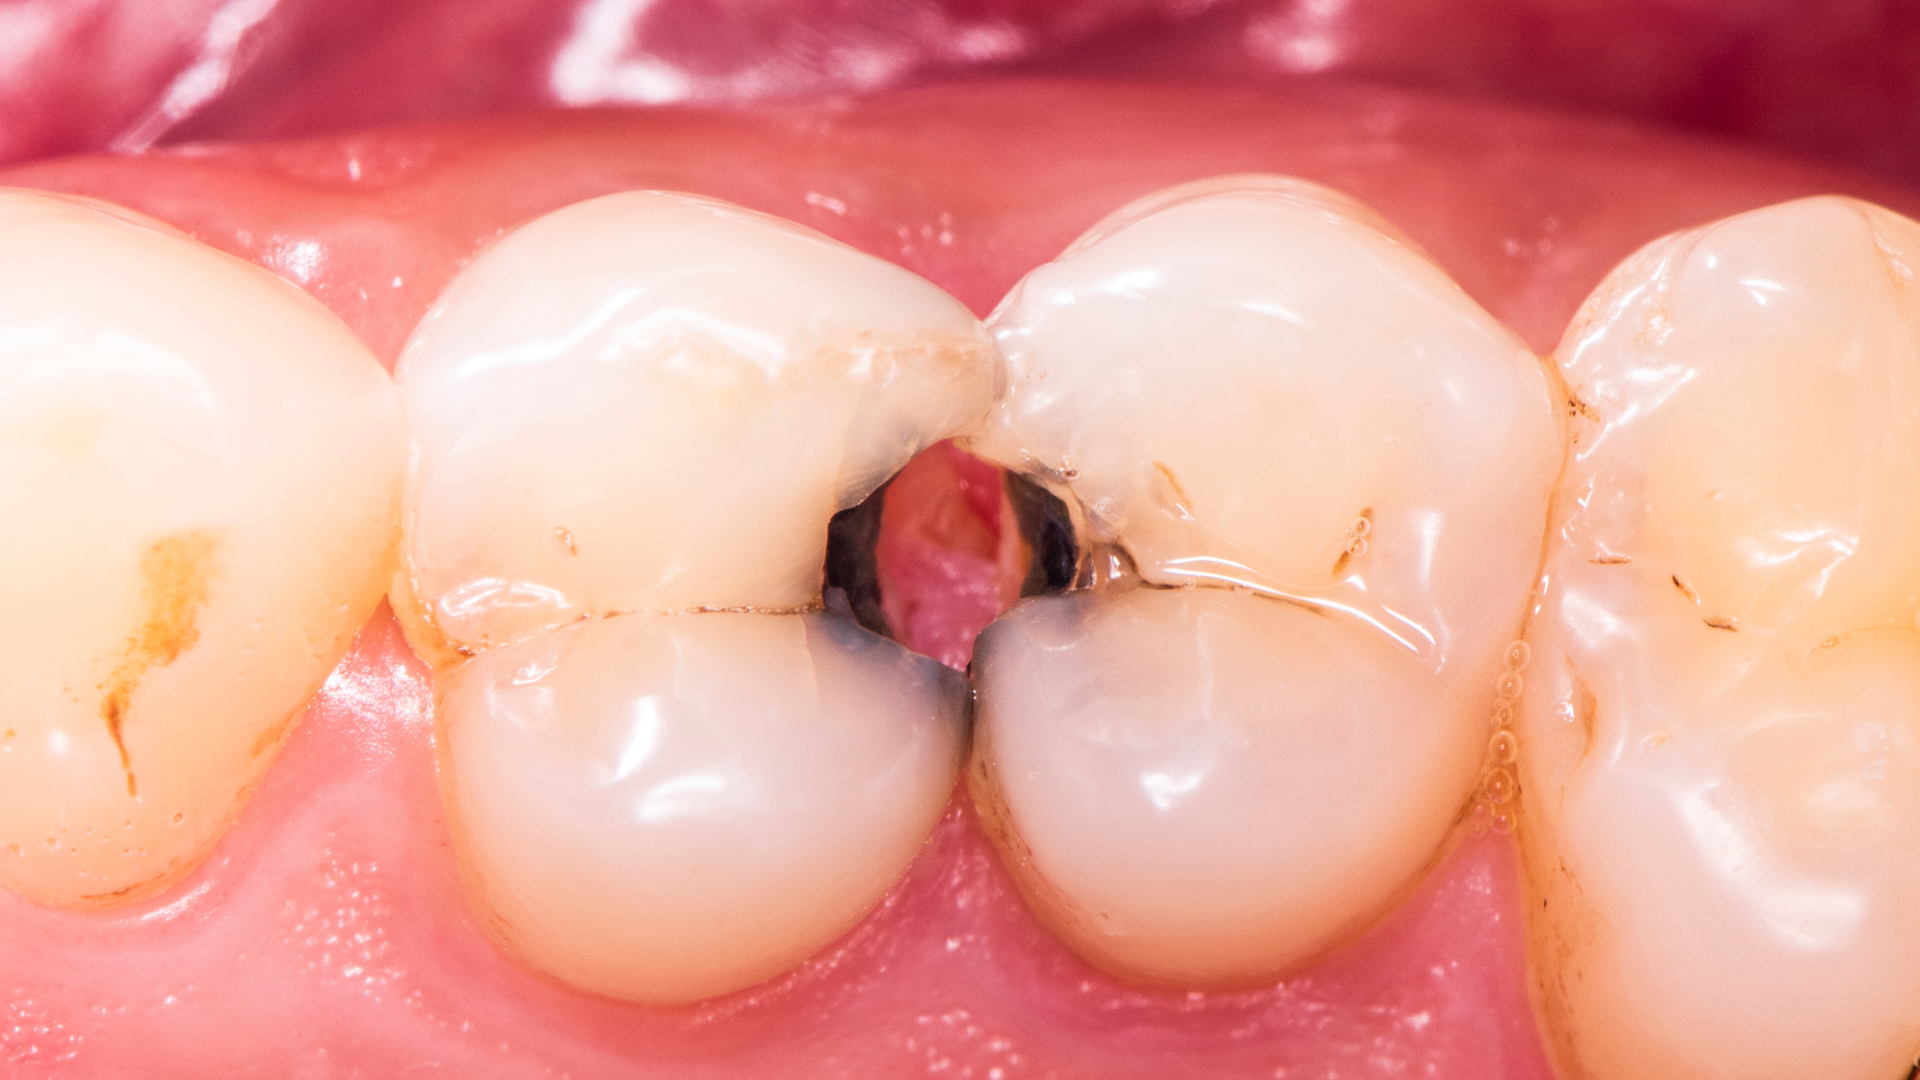

La carie è un processo graduale. All’inizio coinvolge solo lo smalto, senza dare sintomi evidenti. Nessun dolore, nessun fastidio, a volte piccole macchie opache che possono passare inosservate. Quando compaiono i primi segnali, come sensibilità al freddo, al caldo o ai cibi dolci, e fastidio alla masticazione è probabile che abbia raggiunto strati più profondi del dente. Con il tempo infatti, se non intercettata, la carie può coinvolgere la dentina, che si trova subito sotto lo smalto, e poi la polpa, che contiene il “nervo” del dente. A quel punto iniziano i problemi più seri: si sviluppano infezioni, comincia il dolore, il dente perde a poco a poco la sua vitalità e il nervo va in necrosi, rendendo necessaria la devitalizzazione dell’elemento. A questo stadio l’intervento per salvare il dente è più complesso: non è più sufficiente ricostruirlo con un’otturazione estetica in composito, poiché, se il dente ha perso molta struttura, si dovrà intervenire con un intarsio o una corona protesica.

Aspettare il dolore significa quindi intervenire tardi. Un controllo regolare permette di individuare carie iniziali quando il trattamento è più semplice, più rapido e meno invasivo.